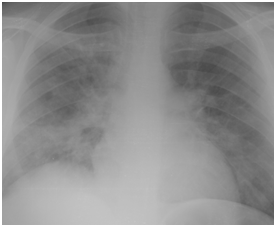

Figure 4A Chest X-ray film on day two from suffering attack of low grade fever.

Figure 4B Follow up Chest X-ray at time of diagnosing H1N1 pneumonia 6 days later.

Figure 4C Follow up Chest X-ray three days after starting oseltamivir therapy.

Figure 4D Follow up chest X-ray after 7 days from starting H1N1 therapy.

Figure 4E Follow up Chest x-ray showing further improvement.

Figure 4F Follow up chest X-ray 4 days after the end of H1N1 therapy.

Figure 4 H1N1 radiological pictures in a diabetic 28-year-old transplant recipient.